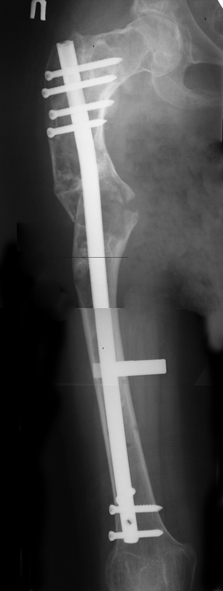

Женщина 28 лет, Больна с 12 летнего возраста, Когда после адекватной травмы получила перелом бедра. На рентгенограммах выявлено какое-то (рентгенограмм и документов нет) изменение бедренной кости, была оперирована, имеется гистологическое заключение - фиброзная дисплазия.дСформировалась деформация бедра. На сегодня - Укорочение 7см. Грубая деформация бедра по типу "пастушьей палки", последний патологический перелом в январе 2004г., консолидировавшийся при консервативном лечении. Имеются грубые изменения и в надвертлужном массиве.-- С уважением, Leonid

Возможна аппаратная коррекция оси с формированием клиновидного регенерата, которая решила бы и проблему укорочения (что, впрочем, нужно уточнить по схеме, сделанной по рентгенограмме с хорошим захватом смежных суставов - схемка по присланному снимку в приложении). По окончании коррекции - блокируемый стержень, который и сократит время пребывания в аппарате, и вообще возврата к нормальной жизни, а также будет мерой профилактики патологических переломов.

Собственно сустав не беспокоит, объем движений полный. По скиаграммам получается, что достаточно одной остеотомии на вершине деформации, чтобы восстановить длину и вывести коленный сустав в нужное положение.

Т.к. укорочение 7 см, то начинать будем с соеотомии и коррекции аппаратом. Спасибо

Уважаемые коллеги! Большое спасибо за живой отклик и предложения по тактике лечения. Больной произведен первый этап - стержневой аппарат издвух баз, кортикотомия, остеоклазия и начата коррекция в аппарате. Почти исправлен угол, не сегодня укорочение 2см. Когда завершим коррекция, представлю рентгенограммы.

Leonid Pollyak 02 Январь 2005, 22:42

В ноябре этого года я обращался с просьбой о помощи в выборе тактики лечения больной с деформацией бедра на почве фиброзной дисплазии. Были получены интересные и очень полезные советы по операции.

Хотелось бы показать, что получилось в результате.

Операция выполнялась с помощью А.Н.Челнокова. Очень понравилась технология выполнения блокируемого остеосинтеза с использованием спицевого дистрактора, модифицированный гвоздь с латерализованным проксимальным отделом и возможностью многовинтовой фиксации проксимального и дистального участков бедра.